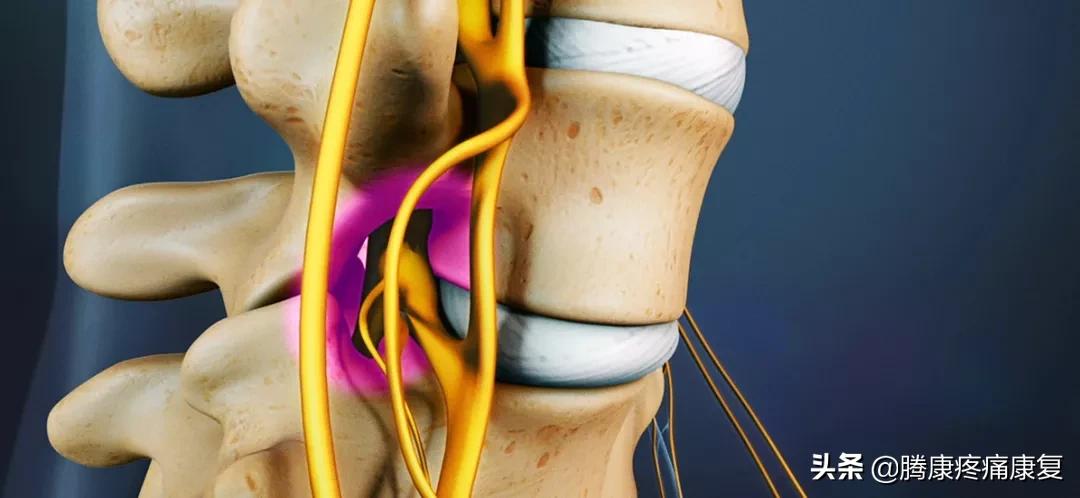

随着年龄增长,腰椎发生退行性改变,椎间盘退变,椎间隙变窄,周围韧带松弛,椎体间骨赘增生,突入椎管导致椎管容积变小;小关节退变,关节囊松弛,小关节增生,上关节突增生导致侧隐窝狭窄,下关节突增生向椎管内聚,导致中央管狭窄;椎板及黄韧带增生肥厚,导致中央椎管狭窄。

此外,合并腰椎间盘突出、退变性滑脱也会导致椎管狭窄。

发生椎管狭窄以后,神经根被增生组织摩擦充血,同时椎管内硬膜外静脉丛回流障碍和椎管内无菌性炎症,引起马尾神经症状或神经根症状。当走路活动时,马尾神经需要的血供增加,静脉回流增加,导致椎管内压力增加,由于椎管狭窄已到了临界程度,动脉供血被迫减少以适应椎管内压力变化,这导致马尾神经缺血而产生下肢疼痛、麻木、无力,此时患者因腿痛而不能再走,需停下休息,马尾神经用血减少,坐下休息或向前弯腰使椎管内容积增大,有利于静脉回流,从而症状消失。